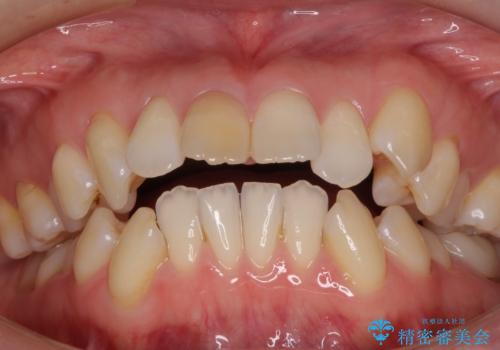

- 上の前歯の飛び出した感じを改善したいとのことで来院された患者様です。

上顎左右第一小臼歯2本、下顎左右第二小臼歯2本を抜歯し、ワイヤー装置にて口元を引っ込めるよう矯正治療を行うこととしました。

上下の前歯に隙間が空くほど上顎前歯が前に飛び出していましたが、抜歯矯正により上下前歯がぴったりと付くほど口元を引っ込めることができました。